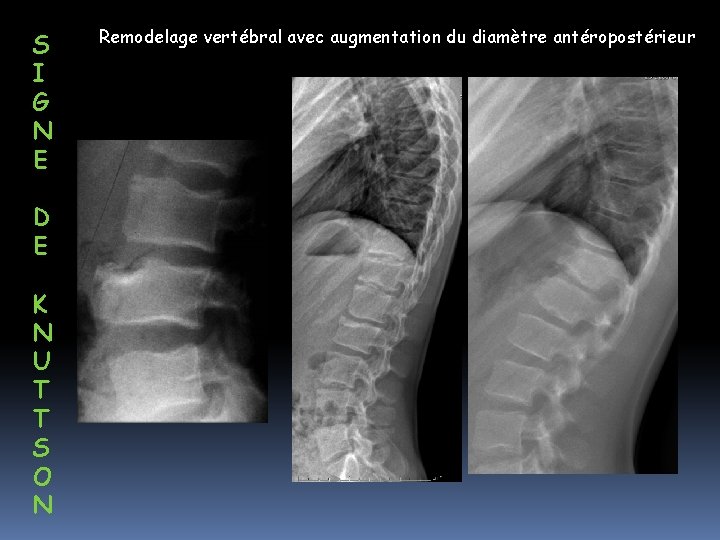

S I G N E D E K N U T T S O N Remodelage vertébral avec augmentation du diamètre antéropostérieur